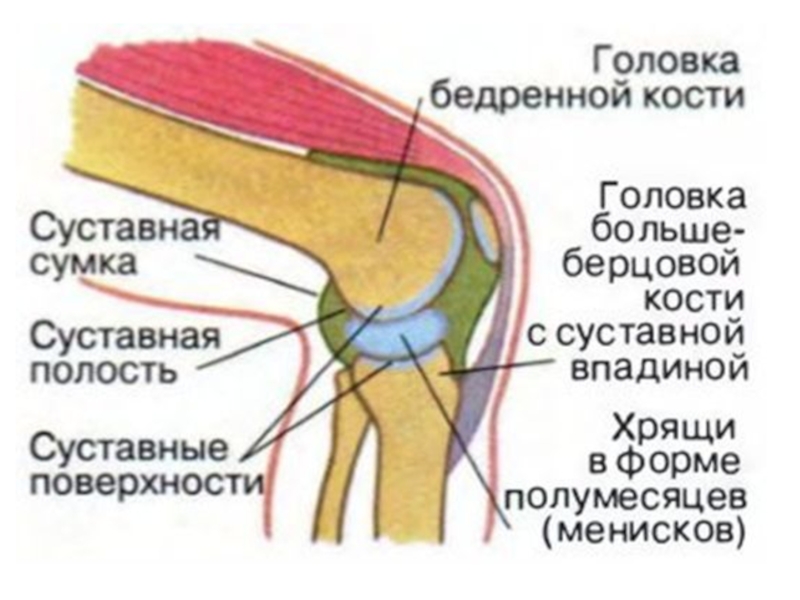

Суставная Жидкость и Головка Сустава: Обзор и Здоровье